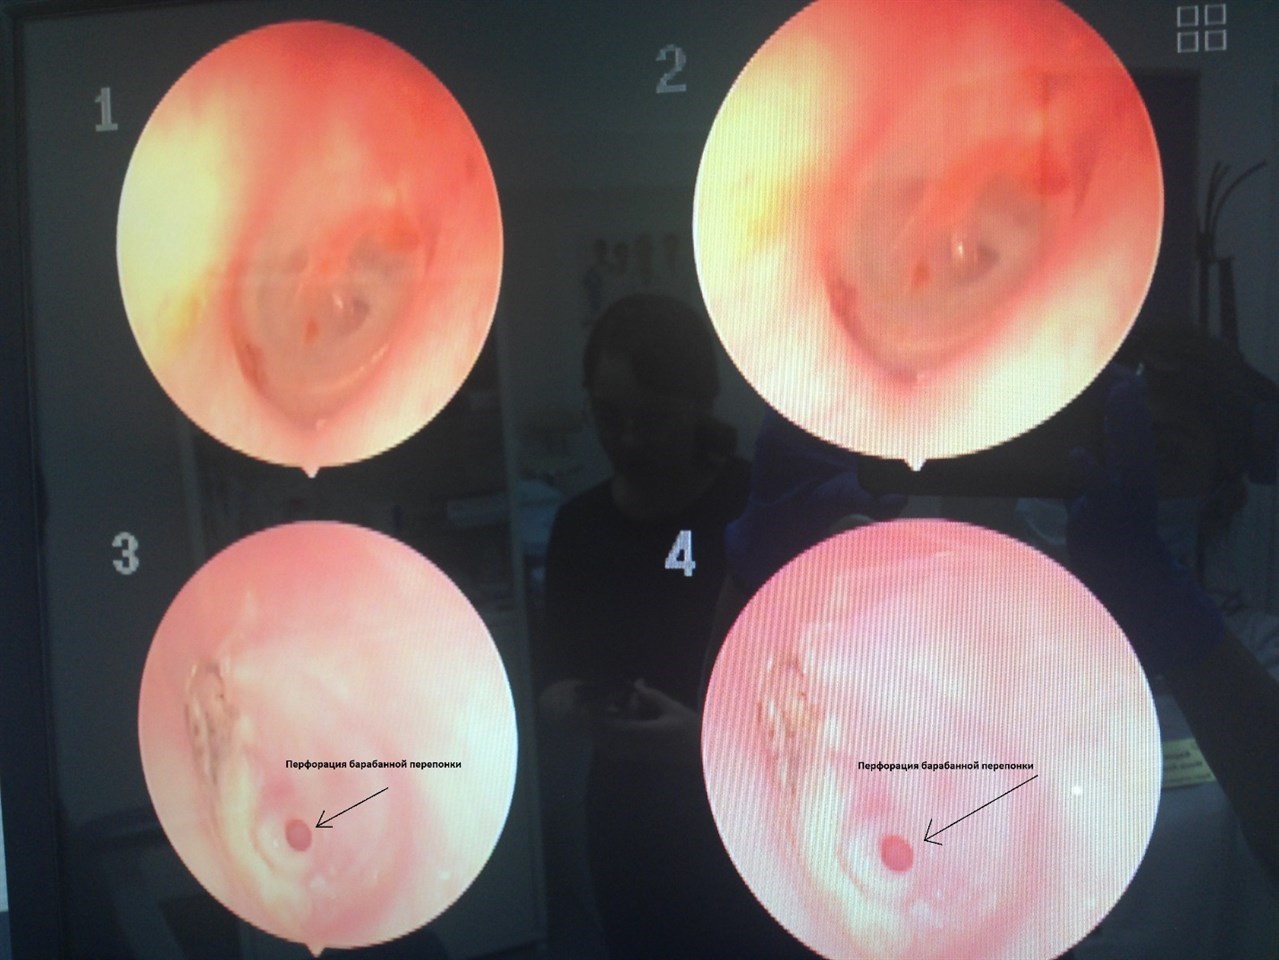

Наличие разрыва барабанной перепонки лор-врач может определить при визуальном осмотре с помощью осветительного прибора (отоскопа, микроскопа или эндоскопа). Врач может проводить дополнительные тесты для определения причины разрыва или степени повреждения. Эти тесты включают в себя:

При подозрении на разрыв барабанной перепонки специалист проводит осмотр внутренних частей уха при помощи отоскопа. При обнаружении повреждения врач назначает специальные ушные капли, которые уменьшают воспаление и обладают антисептическим действием. Некоторые препараты воздействуют непосредственно на место разрыва и способствуют быстрой регенерации повреждённых тканей. В качестве дополнительной терапии назначаются противовоспалительные лекарственные препараты и физиотерапевтические процедуры.